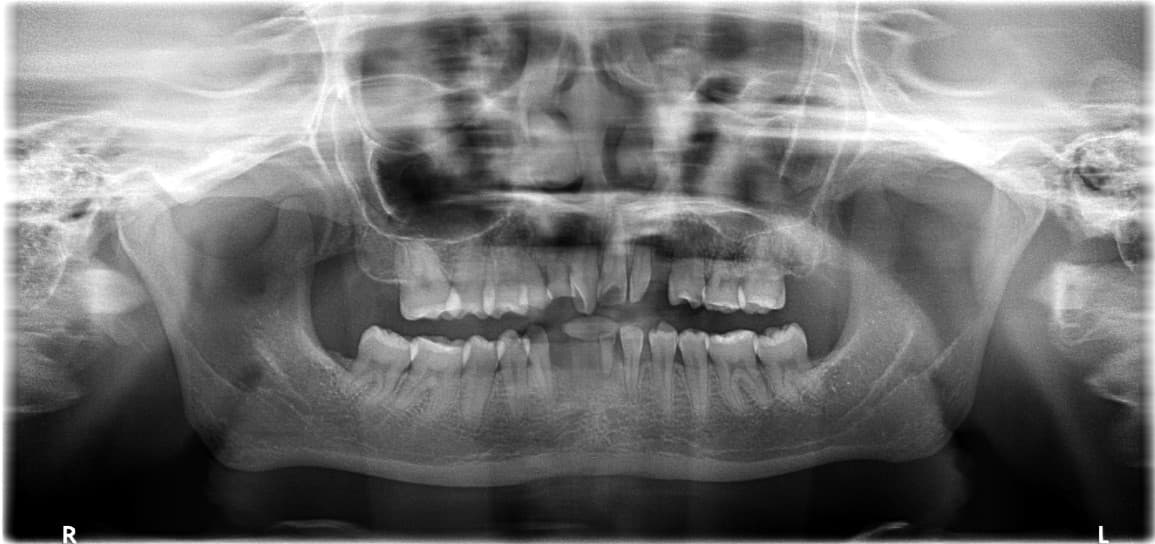

Quét dấu hàm 3D

Chẩn đoán chính xác thông qua máy quét trong miệng

Thiết kế phẫu thuật giả lập

Lập kế hoạch vị trí cấy ghép tối ưu trên máy tính

Đặt máng hướng dẫn

Thiết bị hướng dẫn chính xác với độ sai lệch dưới 1mm

Phẫu thuật xâm lấn tối thiểu

Rút ngắn thời gian, giảm thiểu đau và sưng

Kiểm chứng phẫu thuật

Giảm thiểu sai sót để mang lại sự hài lòng cao nhất

Chẩn đoán kỹ thuật số chính xác đảm bảo chỉ thực hiện các thủ thuật cần thiết tối thiểu.

Phẫu thuật hướng dẫn kỹ thuật số 3D

Cấy ghép chính xác đến 0,1mm Giảm thiểu nguy cơ tổn thương dây thần kinh và mạch máu

Phẫu thuật hướng dẫn kỹ thuật số khác gì so với phẫu thuật thông thường?

Phẫu thuật hướng dẫn kỹ thuật số thực hiện chẩn đoán chính xác bằng quét 3D răng miệng, sau đó tiến hành phẫu thuật ảo trên máy tính trước. Qua đó thiết kế vị trí cấy ghép tối ưu, giảm thiểu sai số đến 1mm và giảm thiểu cắt mô. Kết quả là thời gian phẫu thuật được rút ngắn và giảm thiểu đau, sưng và ghép xương.